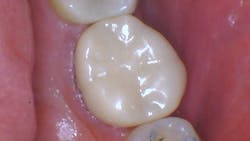

Figure 1: This amalgam has outlasted its usefulness.